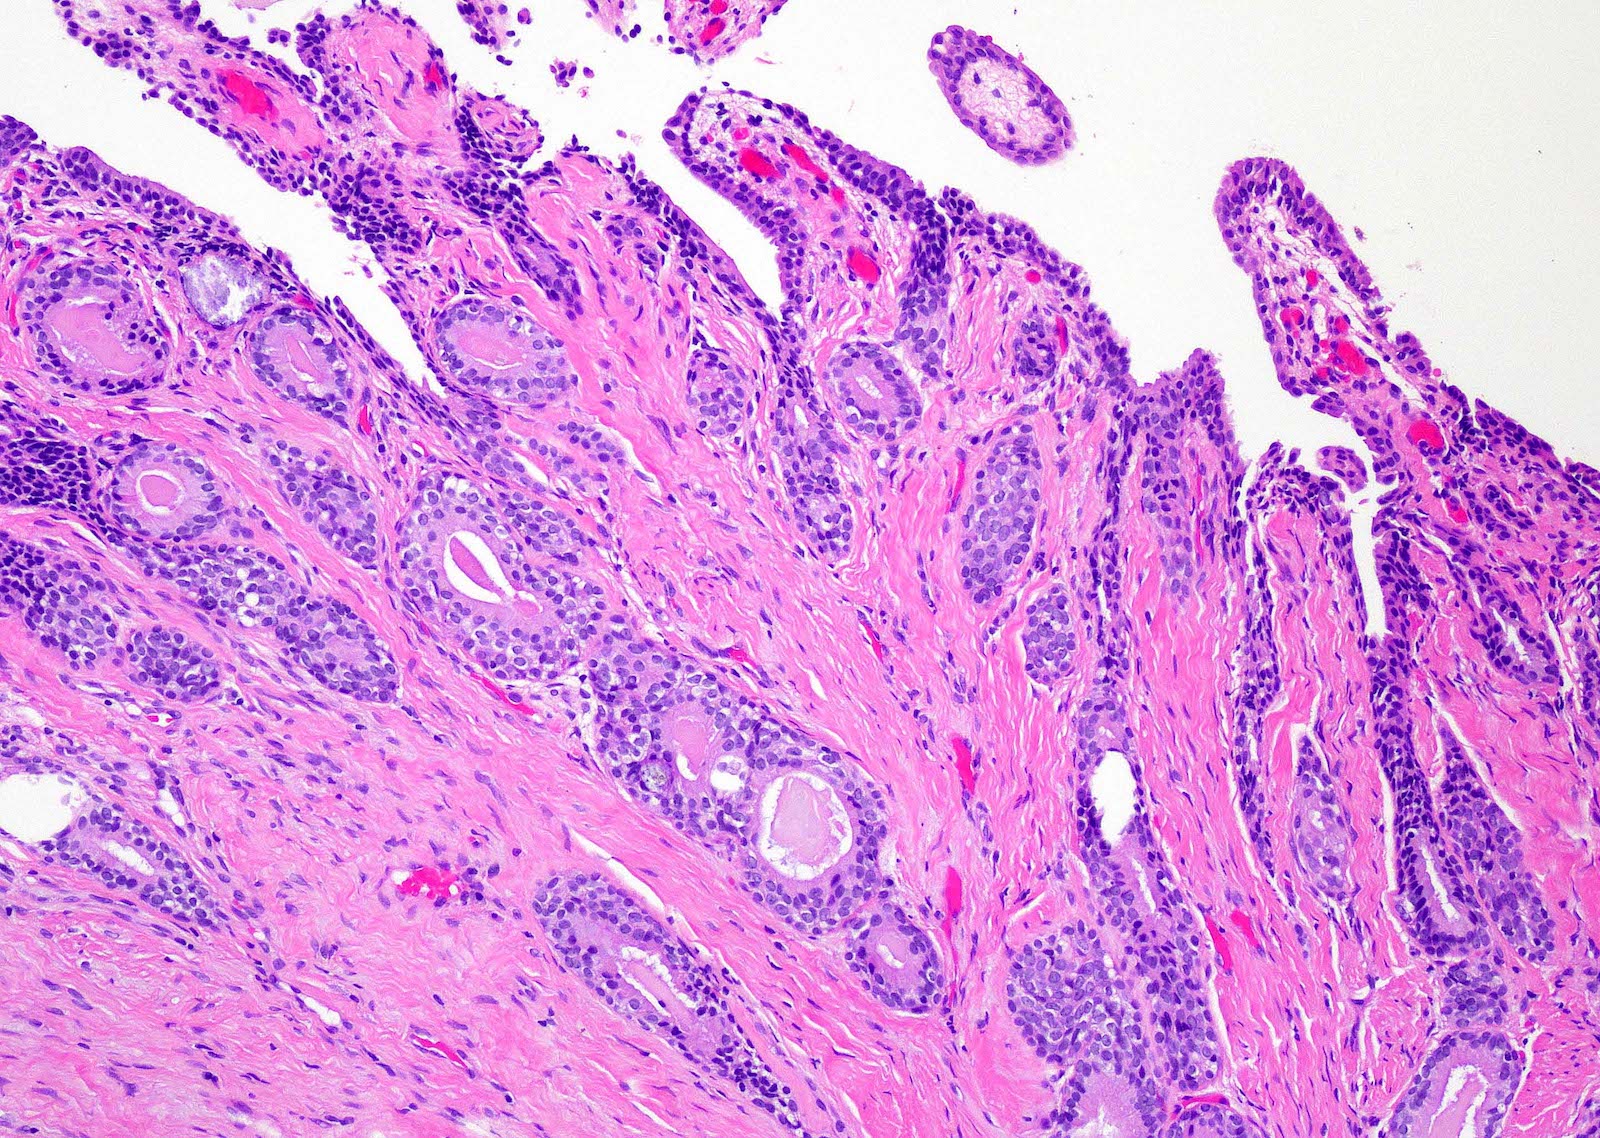

- Fibroepithelial urethral polyp (Am J Surg Pathol 2005;29:460):

- Pattern 1: most common pattern includes the following features

- Broad cloverleaf-like and club-like projections covered by normal urothelium and composed of dense fibrovascular stroma with florid cytitis cystica et glandularis (most common morphologic variant)

- Back to back glands present in the stalk

- Anastomosing nests of benign urothelial cells resembling inverted papilloma

- Dilated cysts with intracystic papillary contents

Microscopic (histologic) images

Contributed by Y. Albert Yeh, M.D., Ph.D.

Fibroepithelial polyp